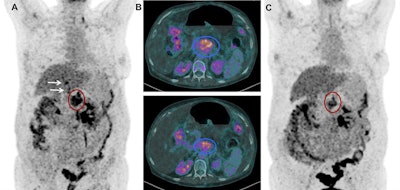

Images show FDG-PET and CT scans of a patient before and after treatment. A: FDG-PET before Lu-177 3BP-227 treatment (red oval: primary tumor; arrows: liver metastases). Upper panel of B: Axial CT section showing primary tumor (blue oval) before therapy. Lower panel of B: Axial CT section after three cycles of Lu-177 3BP-227. C: FDG-PET after three cycles of therapy. Images courtesy of Baum et al and JNM.Lu-177 3BP-227 was well-tolerated by the patients, the researchers found. In addition, one patient experienced significant improvement of symptoms and quality of life, surviving 13 months from diagnosis and 11 months from the start of therapy with Lu-177 3BP-227. The five-year survival rate for patients with this type of cancer is less than 5%.